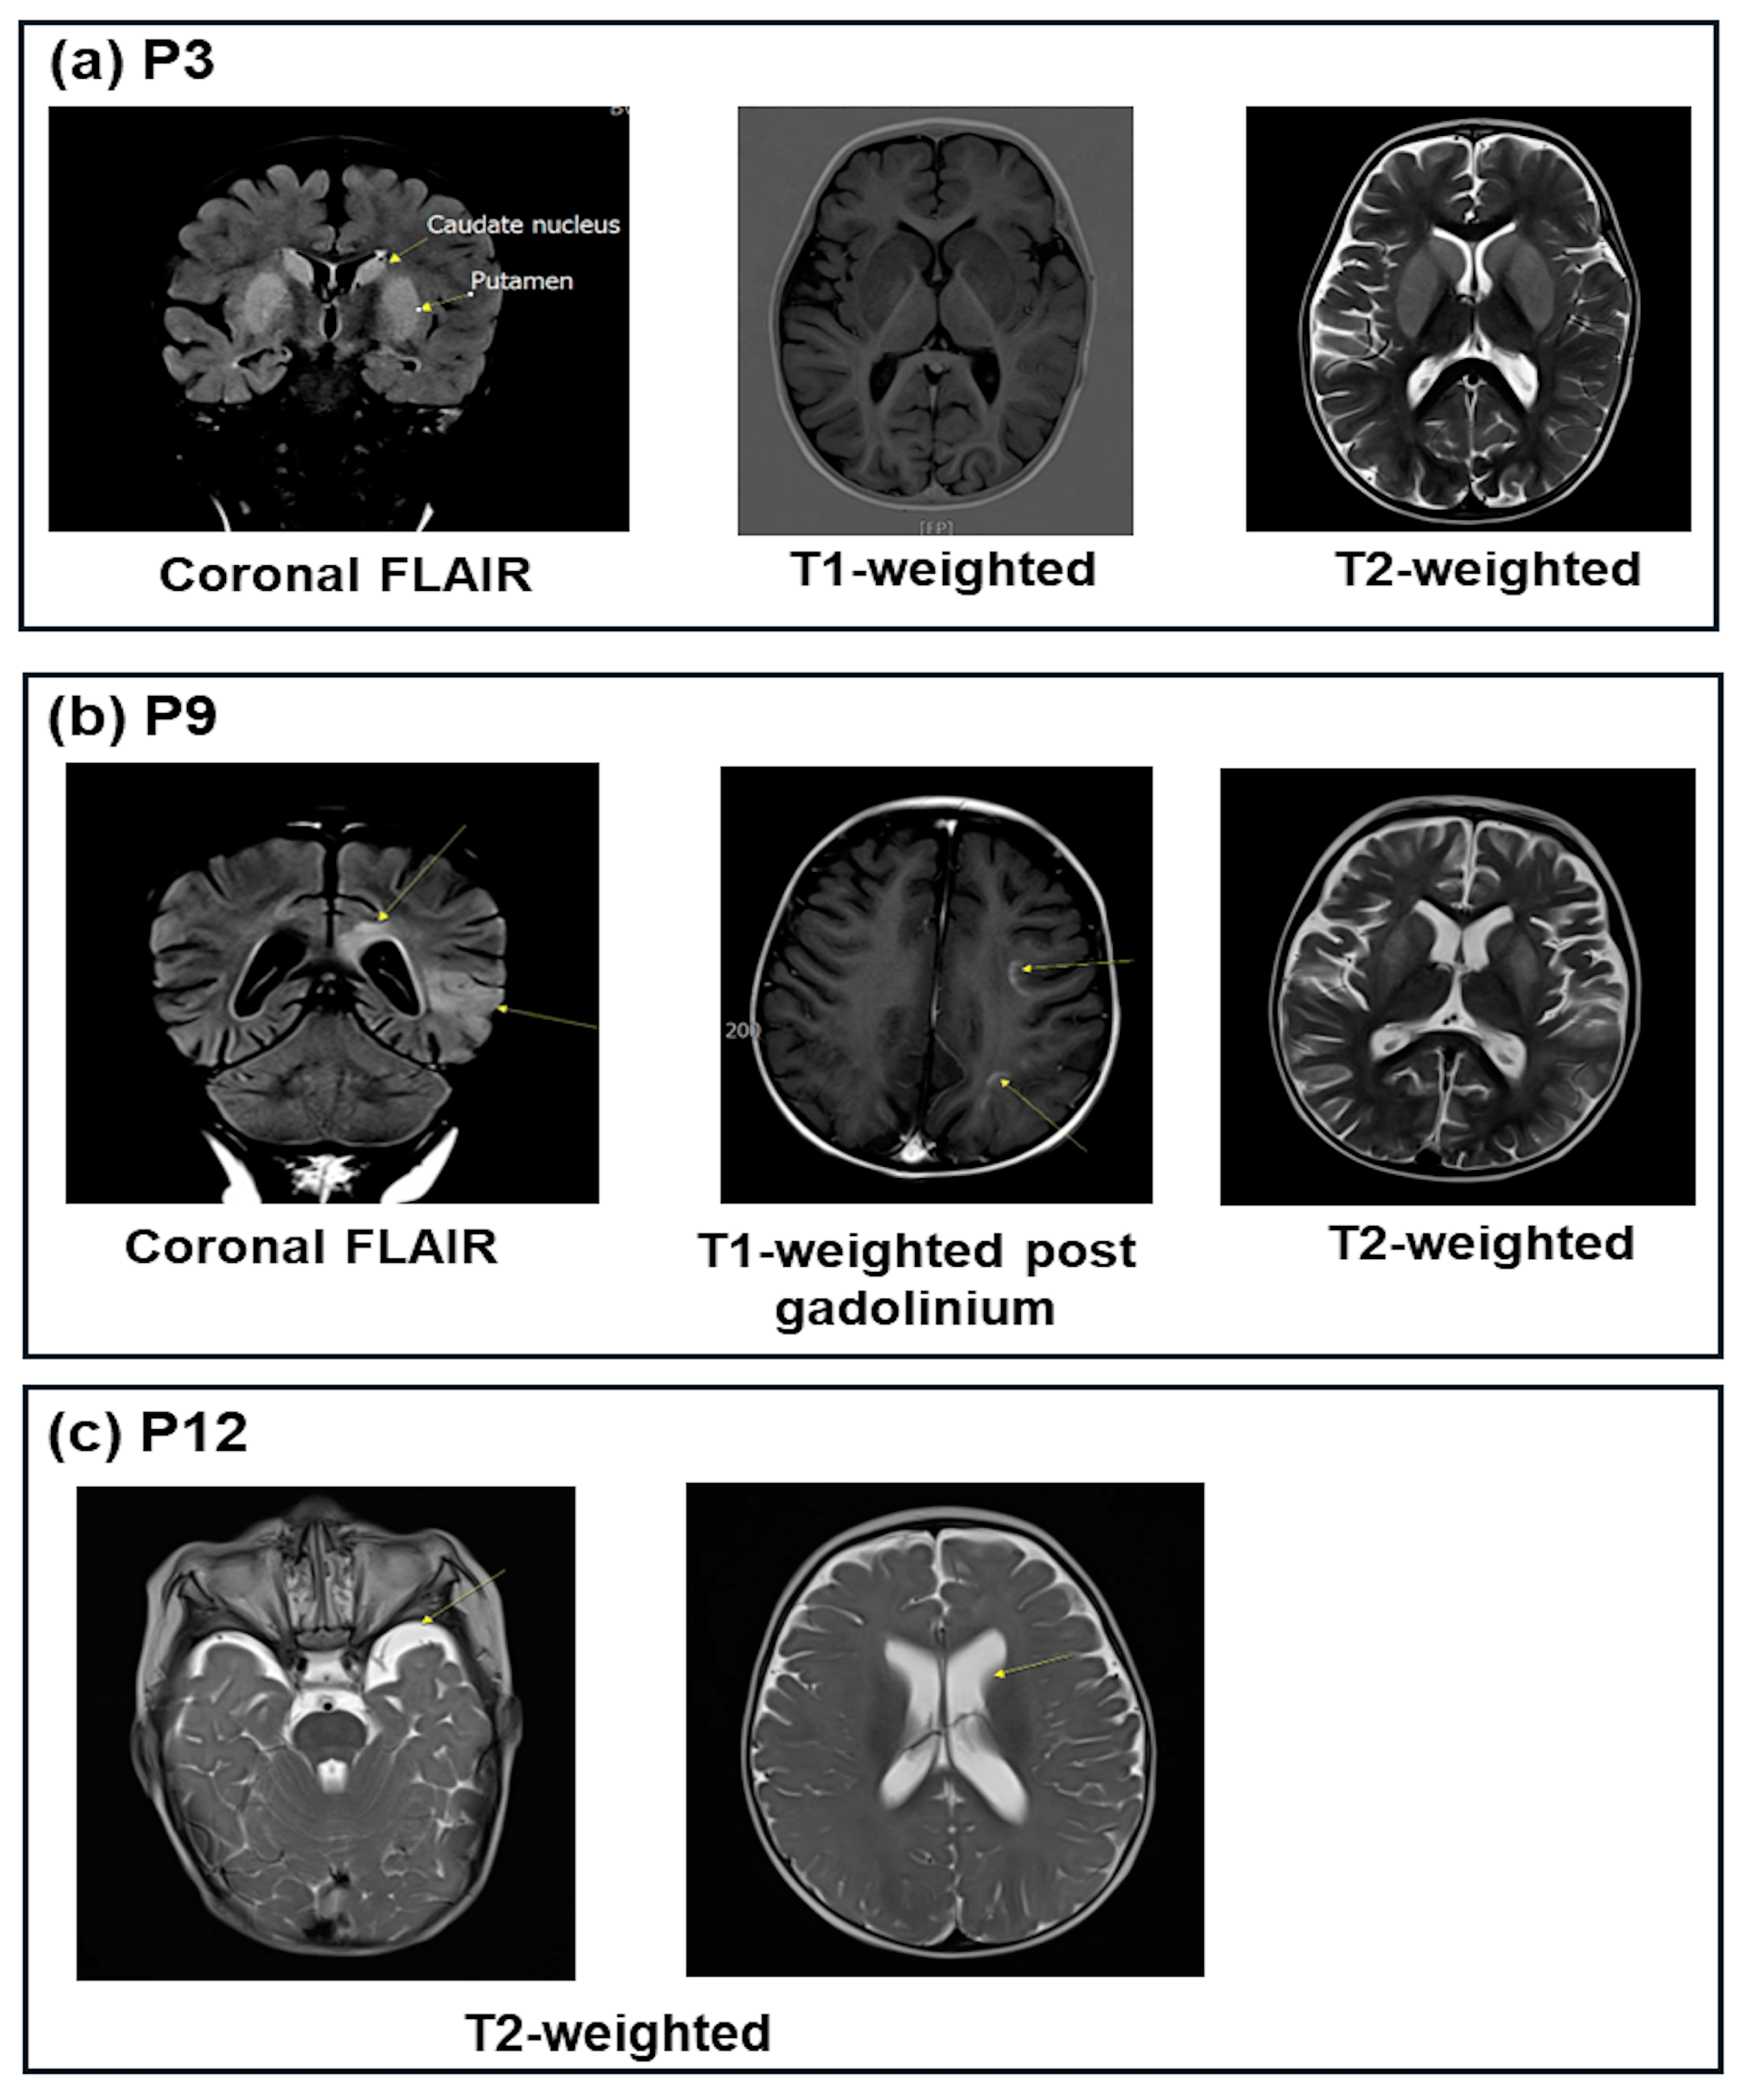

| P3 | ↓0.8 | 7.12 | 9.6 | -21.0 | 51.6 | ↑108 | ↑209 | ↑2287 | ↓4.4 | 27.0 | - | 1+ | Lesions of the bilateral putamen caudate |

| P9 | 3.82 | 7.00 | 8.6 | -20.0 | 49.2 | ↑126 | ↑143 | NA | 16.7 | 8.8 | - | Neg | Bilateral cerebrum lesions |

| P12 | ↓2.48 | 7.37 | 7.5 | -15.6 | 36.4 | ↑132 | ↑270 | NA | ↓3.8 | 19.7 | - | 1+ | Slight ventilation dilation |